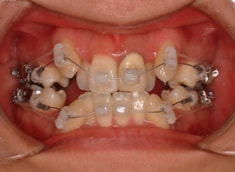

治療開始から約1年後

治療法:表の矯正(T21ブラケット)